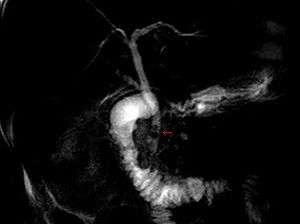

| MRCP image of two stones in the distal common bile duct | |

The diagnosis of choledocholithiasis is suggested when the liver function blood test shows an elevation in bilirubin and serum transaminases. Other indicators include raised indicators of ampulla of vater (pancreatic duct obstruction) such as lipases and amylases. In prolonged cases the INR may change due to a decrease in vitamin K absorption. (It is the decreased bile flow which reduces fat breakdown and therefore absorption of fat soluble vitamins). The diagnosis is confirmed with either an MRCP (magnetic resonance cholangiopancreatography), an ERCP, or an intraoperative cholangiogram. If the patient must have the gallbladder removed for gallstones, the surgeon may choose to proceed with the surgery, and obtain a cholangiogram during the surgery. If the cholangiogram shows a stone in the bile duct, the surgeon may attempt to treat the problem by flushing the stone into the intestine or retrieve the stone back through the cystic duct.

On a different pathway, the physician may choose to proceed with ERCP before surgery. The benefit of ERCP is that it can be utilized not just to diagnose, but also to treat the problem. During ERCP the endoscopist may surgically widen the opening into the bile duct and remove the stone through that opening. ERCP, however, is an invasive procedure and has its own potential complications. Thus, if the suspicion is low, the physician may choose to confirm the diagnosis with MRCP, a non-invasive imaging technique, before proceeding with ERCP or surgery.